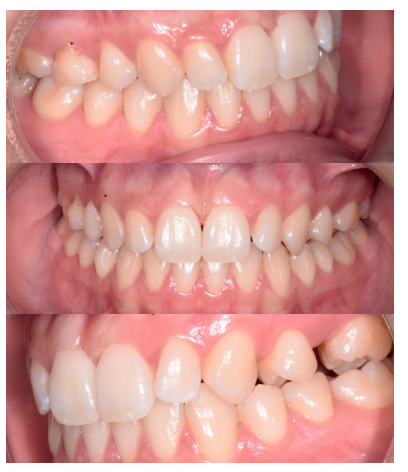

Se presenta un caso clínico de una mujer de 20 años de edad, que acudió remitida por su ortodoncista para la extracción de un premolar retenido maxilar, en posición invertida, previo a la realización de tratamiento ortodóntico. Se realizó la Historia Clínica de la paciente, que no presentó antecedentes médico-quirúrgicos de interés, alergias medicamentosas conocidas ni hábitos nocivos. A la exploración extraoral no se apreció ningún dato relevante. A la exploración intraoral, la paciente presentó la ausencia en boca del segundo premolar superior izquierdo y la presencia de los terceros molares inferiores retenidos (Figuras 1, 2 y 3).

A los diez días se retiró la sutura (Figura 20), donde se puede observar una buena cicatrización de los tejidos blandos. A los 4 meses se realizó una revisión, clínica (Figura 21) y radiográfi ca, mediante radiografía panorámica (Figura 22) y un escáner de haz cónico (Figura 23), donde se puede apreciar la integración del material de injerto y una densidad ósea similar al hueso adyacente, derivando de nuevo a la paciente para comenzar el tratamiento ortodóntico.